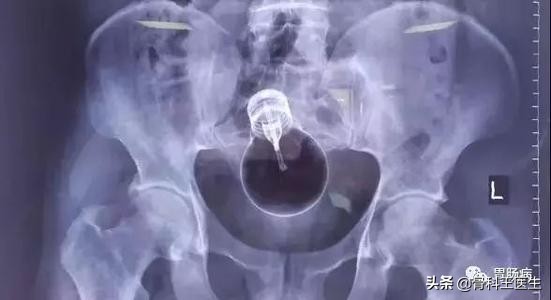

看到了没?自行车手把!

当时没有拍摄,取出的东西送病理去了,和上图差不多!

我的天呐!你没有看错,就是这个东西,我居然是把肚子切开,从病人的肠子里掏出来的!

后来追问病史才知道,患者是5年前吸毒后吞下去的!

这东西在胃里不做怪,可是过了5年掉到肠子里这病人就受不了了才来取的!